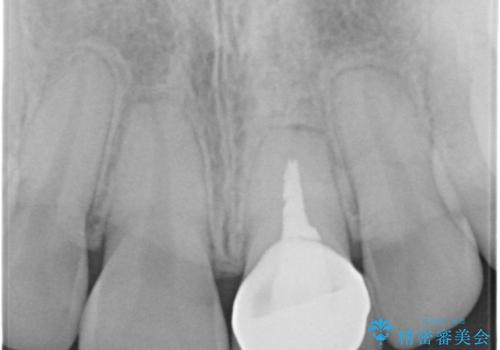

- 「左上の前歯の色が変色し、セラミッククラウンで治したい」とのことで、来院された患者様です。過去に神経の治療(根管治療)をされており、それにより歯の色が変色していました。

左上の前歯(左上1)は、歯の形を整えてオールセラミッククラウンという被せ物で、変色の改善を行いました。

変色していた左上の前歯は、過去に神経の治療(根管治療)をされており、それにより歯の色が変色していました。

根管治療を行った歯は、破折するリスクがあるため、被せ物をすることで、破折リスクの軽減にもなるため、被せ物で歯の色の改善を行いました。